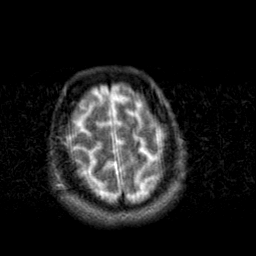

Creutzfeld-Jakob disease: T2-weighted MR -- Slice #20

[Home][Help][Clinical] Slice 20